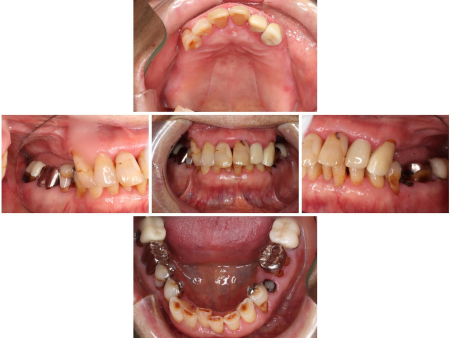

- 当院は、患者様の歯をできるだけ残し、長期的に再治療を防ぎ、質の高い健康を維持することを基本方針としています。

そのため「精密さ・耐久性・生体へのやさしさ」を重視した体制をとっており、原則として自由診療の治療をご提案しています。

一方、自由診療では個々の症例に合わせた治療設計、先進的な材料・技術の使用、再発予防を見据えた治療が可能です。